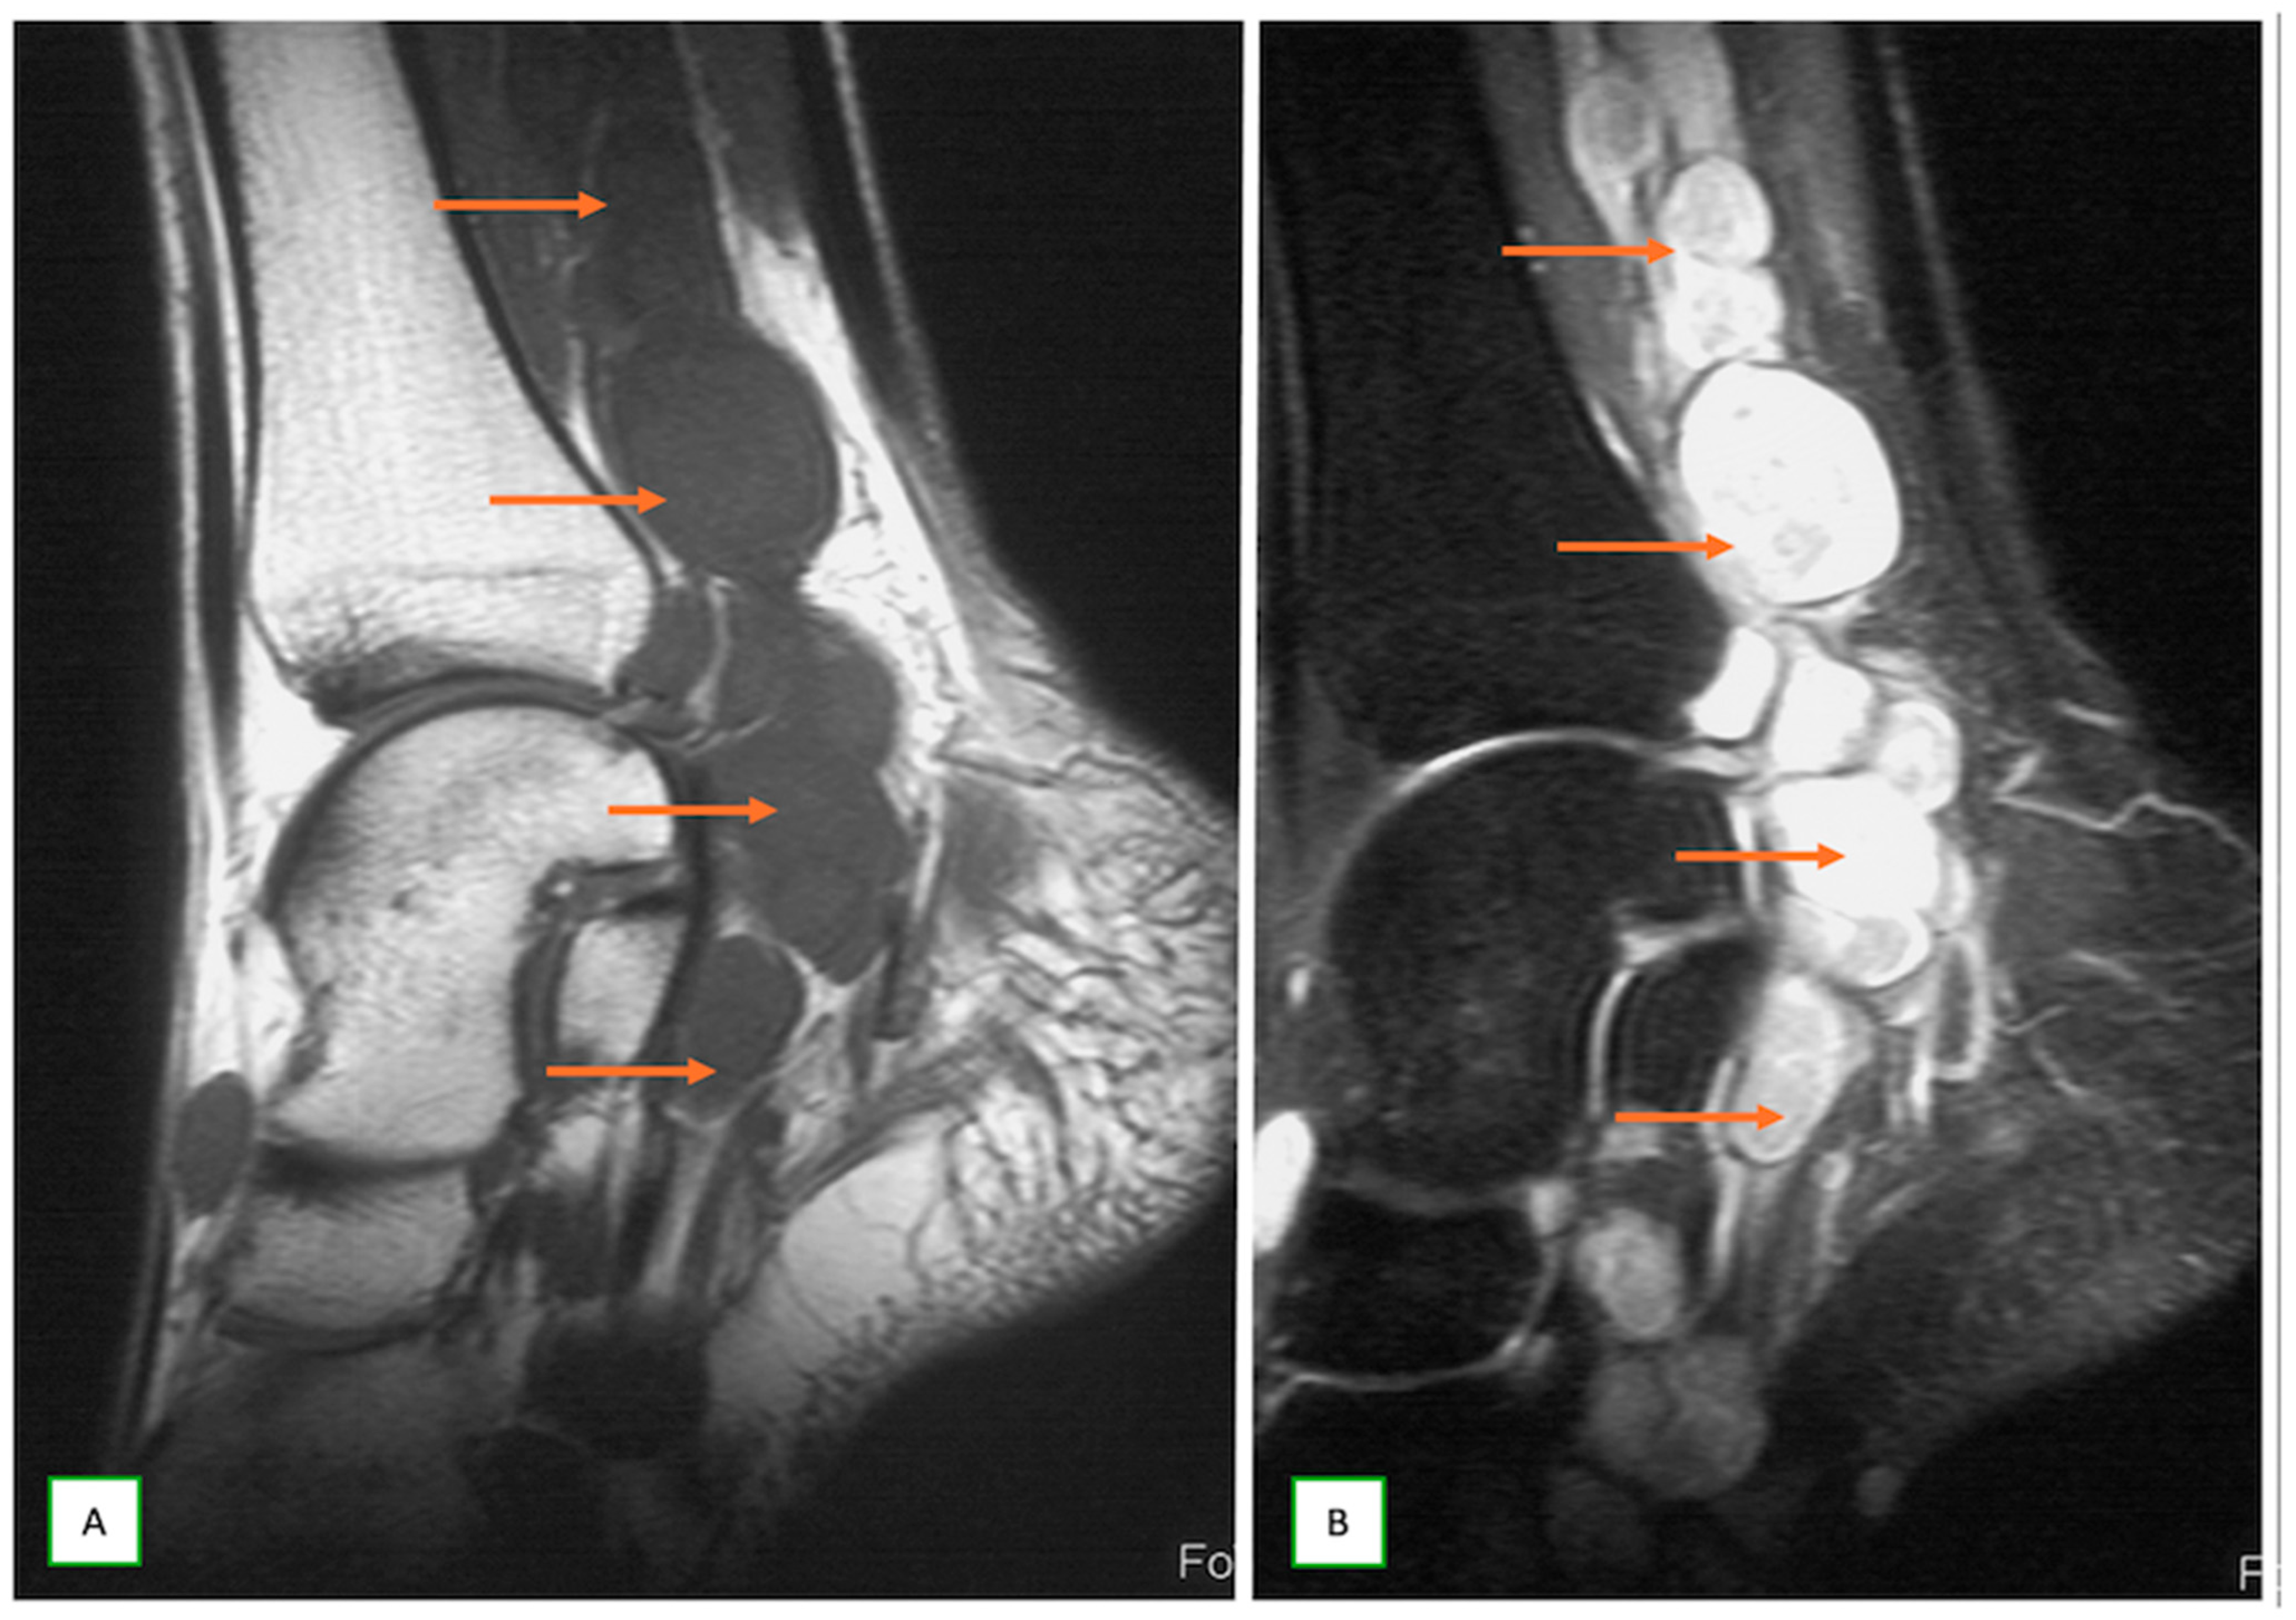

- Intraneural ganglion cysts usually occur near joints; are particularly common in the common peroneal nerve at the knee, owing to the intraarticular branch of the proximal tibiofibular joint; and appear as tubular, multiloculated cystic lesions following the course of the nerve on MRI [60,61] (Figure 16).